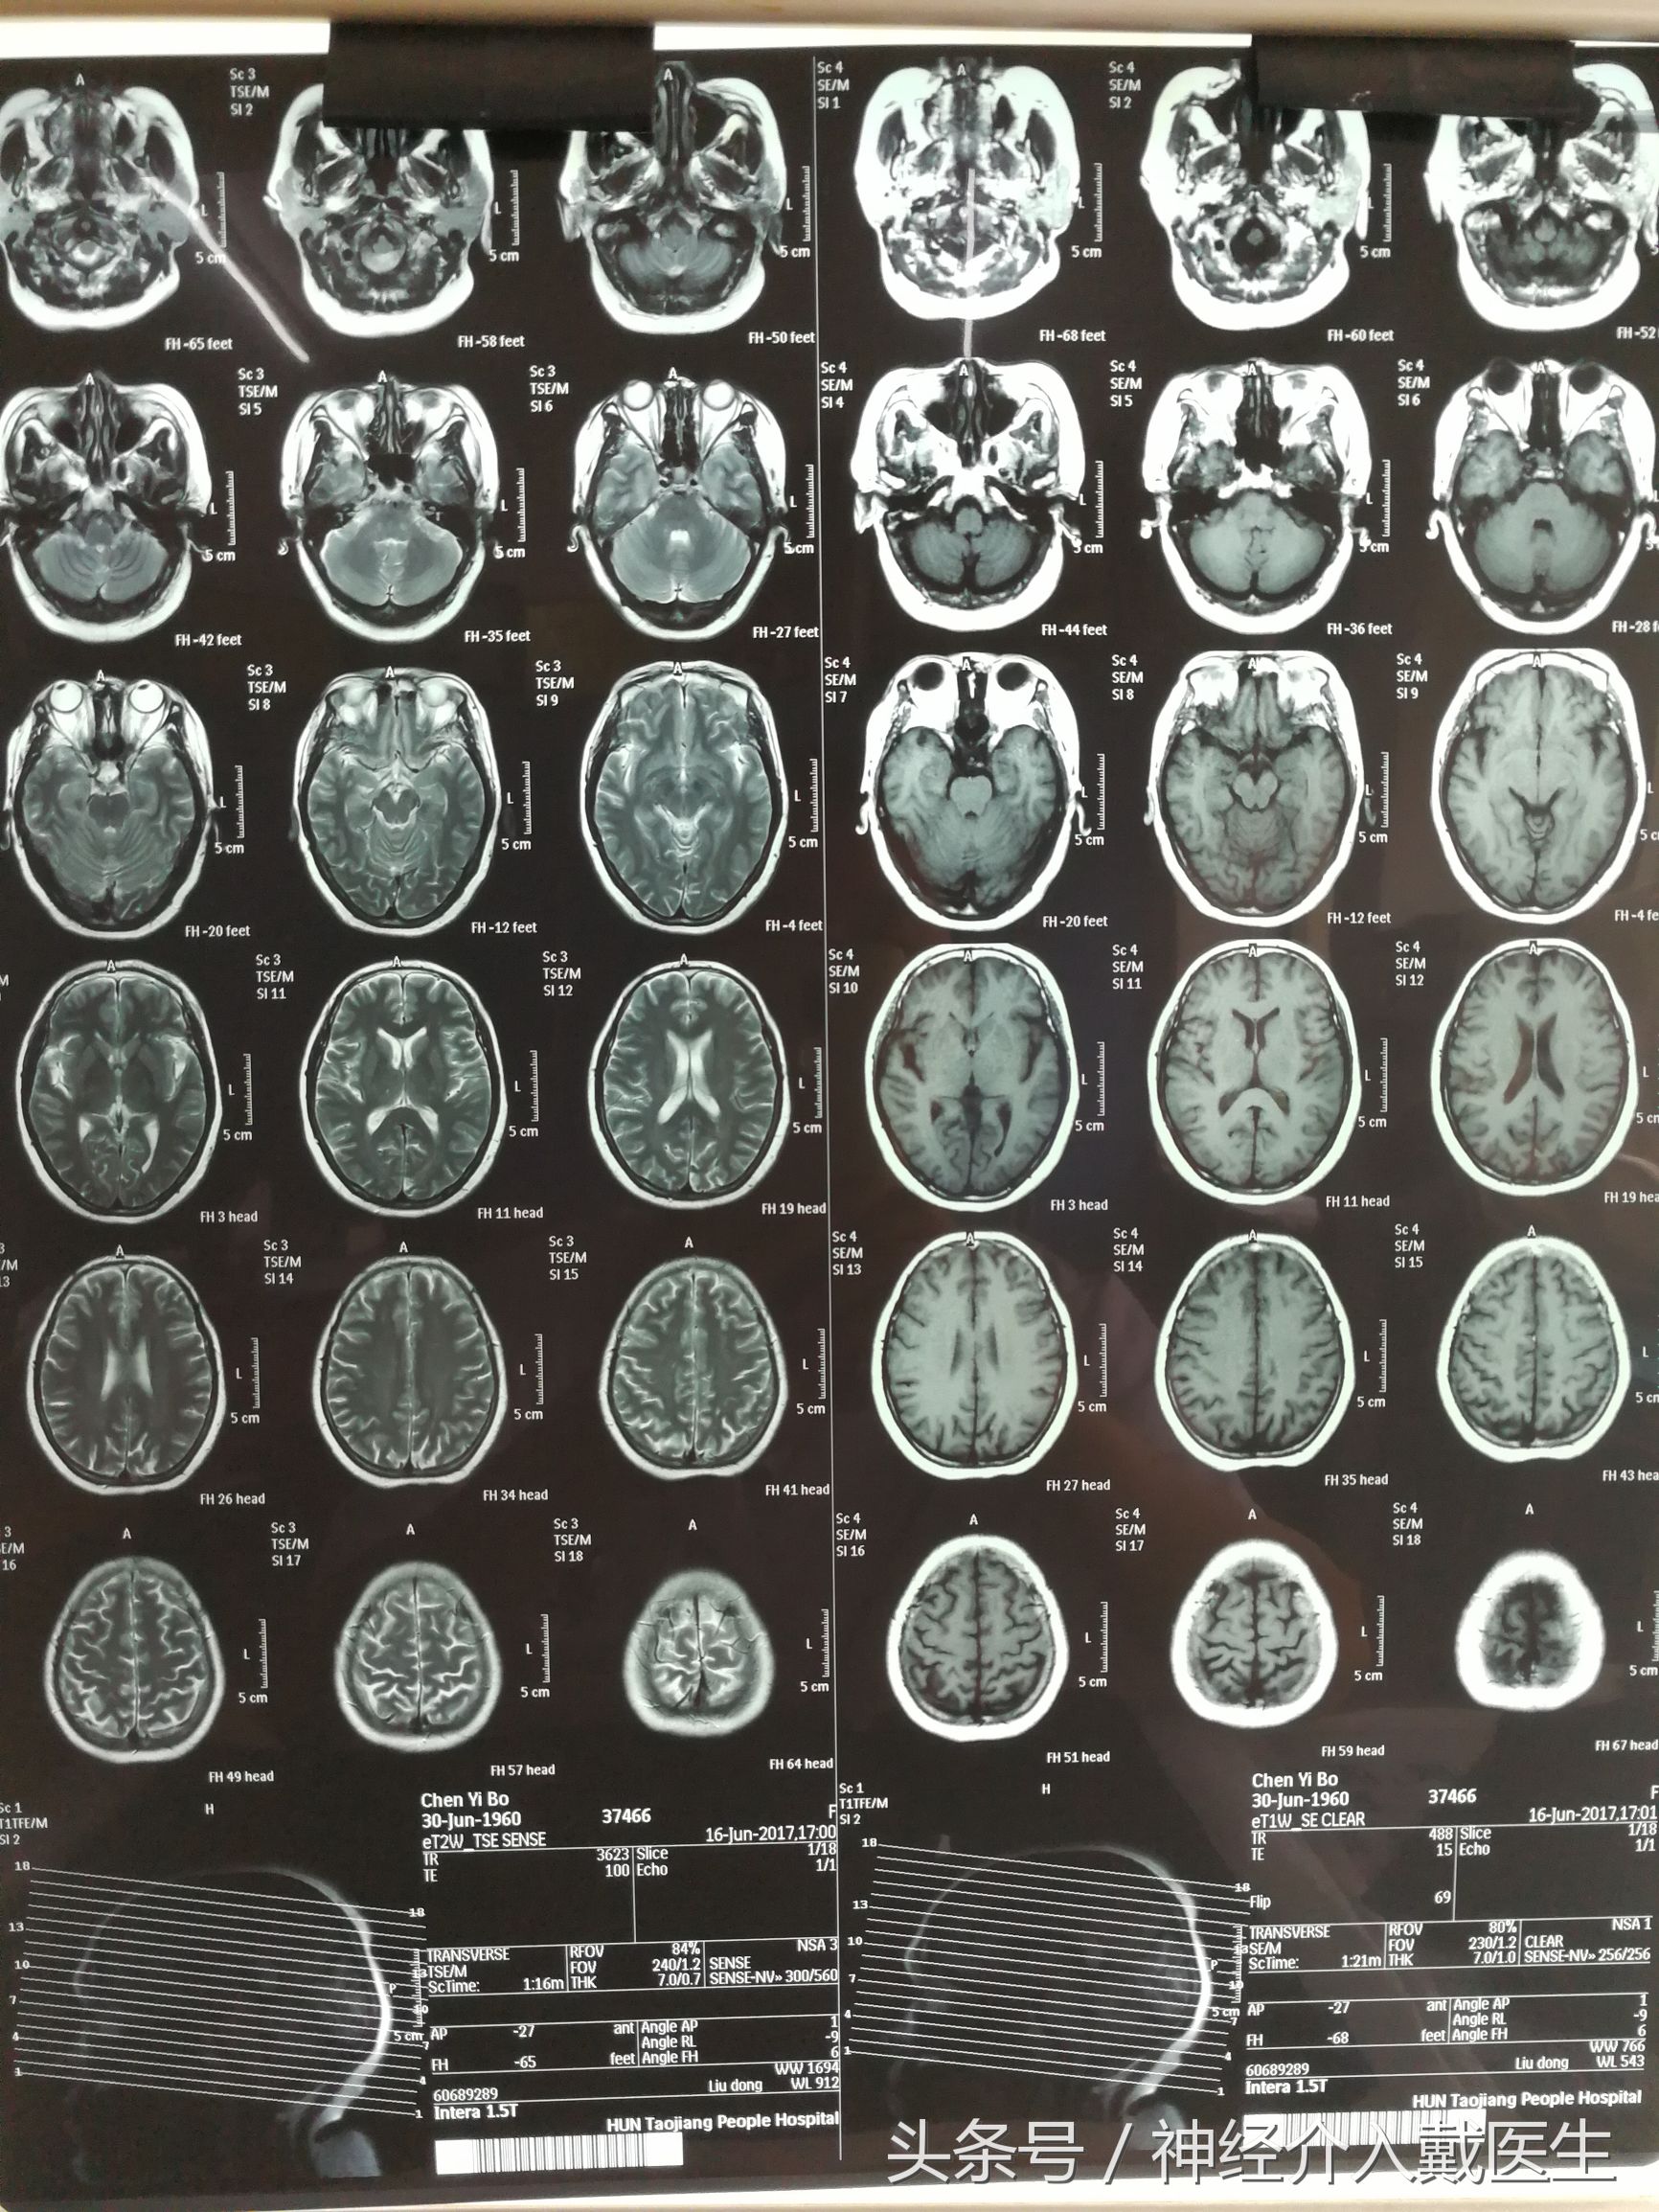

58岁的黄嗲嗲,最近十多天以来,经常无缘无故头晕,有时候还倒在地上,这两天这样的感觉越来越严重了,黄嗲嗲以前长期抽烟,以为是这个原因,把烟戒了以后,也没有什么好转。这不只好到医院来检查,怀疑颅内有问题,做了一个核磁共振。

好像没有发现什么脑梗塞一类的问题。去做了个颈动脉彩超,一下找到罪魁祸首了,颈内动脉狭窄达85%。这个要治疗啊 !进一步必然发生脑梗塞,可能危及生命,这个病需要做脑血管造影进一步评估。